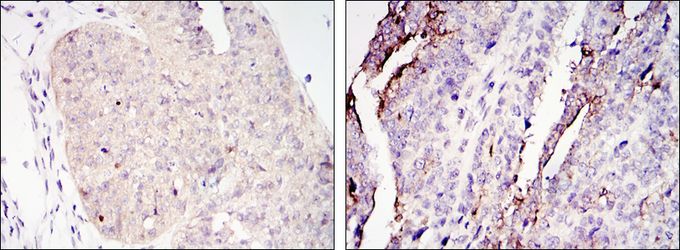

IHC-P analysis of ovary tumour tissue (left) and lung cancer (right) using GTX82754 TORC2 antibody [5B10].